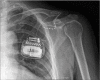

Peripheral nerve stimulation (PNS) is a useful treatment for chronic pain, but it can cause damage depending on its application site. Here, we describe the case of a 54-year-old man who underwent PNS for brachial plexopathy in 2015. One lead was implanted on the left medial cord to stimulate the medial antebrachial cutaneous nerve, and the other was implanted on the radial nerve to stimulate the posterior antebrachial cutaneous nerve. Both leads were inserted near the shoulder joint but did not cross it. Before PNS, the patient did not move his shoulder and elbow because of severe pain, but the treatment greatly alleviated this pain. Twenty months after the operation, both leads were fractured, and the severe pain returned. Repetitive motion near the joint was closely related to the lead fractures. In conclusion, large joints as the insertion sites of PNS leads should be avoided to prevent lead fractures.